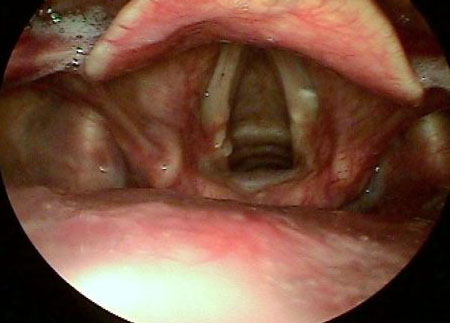

Granulomas nas pregas vocais se formam como resultado de um trauma prolongado e recorrente (fonotrauma ou pós-intubação) e de uma irritação ácida (secundária ao refluxo laringofaríngeo) na glote posterior e pregas vocais.[12] Há uma alta taxa de recorrência de granulomas pós-tratamento se a causa subjacente não for eliminada.[Figure caption and citation for the preceding image starts]: Granuloma 1Do acervo da University of Wisconsin School of Medicine and Public Health [Citation ends].

[Figure caption and citation for the preceding image starts]: Granuloma 2Do acervo da University of Wisconsin School of Medicine and Public Health [Citation ends].